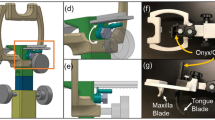

To create a CAD model of the oral stent, a digital “impression” of the dentition was created from the maxillo-mandibular relationship described previously. A rectilinear volume template was overlaid with the dentition with visual verification to ensure all of the occlusal surfaces were within the selected region. Negative impressions of the patient’s dental anatomy with the desired mouth opening were obtained through Boolean subtraction of the patient’s dental anatomy from the rectilinear template. The excess material from the impression block was digitally removed to create the desired structure of the stent followed by post-processing steps to smooth the stent surfaces in contact with the oral mucosa. The major stages of the oral stent design process are depicted in Fig. 3.

Graphical depiction of the process by which the stent is created from the 3D CAD maxillo-mandibular model. a) The rectangular template is overlaid with the mandibular and maxillary dentition to ensure coverage of the entire occlusal surfaces. b) The digital impression of the dentition with the selected incisal opening is created through Boolean subtraction of the patient’s dental anatomy from the template. c) Removal of the excess material to produce a mouth-opening, tongue-depressing stent. d) Smoothing of the external surfaces of the stent created in c) to produce the final product ready for 3D printing

The CAD model of the oral stent was fabricated using the commercially-available Form 2 stereolithography printer (Formlabs Inc., Somerville, MA). Prior to printing, the STL file of the stent was uploaded to the PreForm software package (Formlabs) and manually positioned and oriented to minimize support structure attachment to the surfaces in contact with either the teeth or oral mucosa. This was performed both to minimize potential discomfort caused by local irregularities in contact with the oral mucosa as well as to prevent local geometric distortion of the stent near the support attachment sites which could reduce the fidelity of the stent-occlusal surface junction. The stent was printed using a Formlabs standard clear resin with a 50-μm layer thickness. After completion of printing, post-processing steps including removal of the support structures, washing and removal of residual uncured resin followed by sanding and polishing of the stent surfaces were performed to produce the final product shown in Fig. 4.